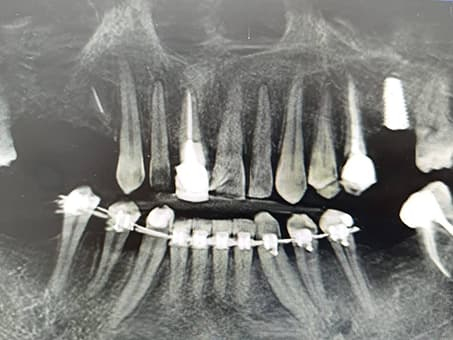

Важной частью услуги цифровой имплантации является интраоральное сканирование зубов. С его помощью можно создать снимки высокой точности, на основании которых изготавливают направляющие для имплантации и капы для исправления прикуса. Сканирование интраоральным сканером показано в случае необходимости изготовления коронок, тотальных конструкций, мостовидных протезов, съемных конструкций и имплантов. Благодаря технологии 3D сканирования зубов можно максимально точно оценить здоровье пациента — пропорции и состояние челюсти, наличие повреждений и составить наиболее эффективный план лечения.

- Диагностика. Доктор собирает анамнез, делает трехмерные снимки челюсти и ротовой полости.

- 3D моделирование. На основании полученных снимков создается объемная модель челюсти по которой доктор оценивает расположение зубов и анализирует состояние тканей.

- Планирование. В специальной программе определяется наиболее подходящее место для установки протеза, рассчитывается угол наклона, длина и тощина импланта с учетом расположения соседних зубных единиц и той нагрузки, которая будет воздействовать на протез.

- Разработка навигационного шаблона для имплантации. В программе создается трафарет, повторяющий все изгибы и рельефы тканей и печатается на 3D принтере.

- Установка имплантов. На этом этапе устанавливается навигационный шаблон, задающий инструментам правильное и точное направление. Имплант устанавливается без разреза или травмирования десны через точечный прокол.

- Установка коронки. После приживления импланта (через 1-6 месяцев после процедуры) устанавливается коронка.